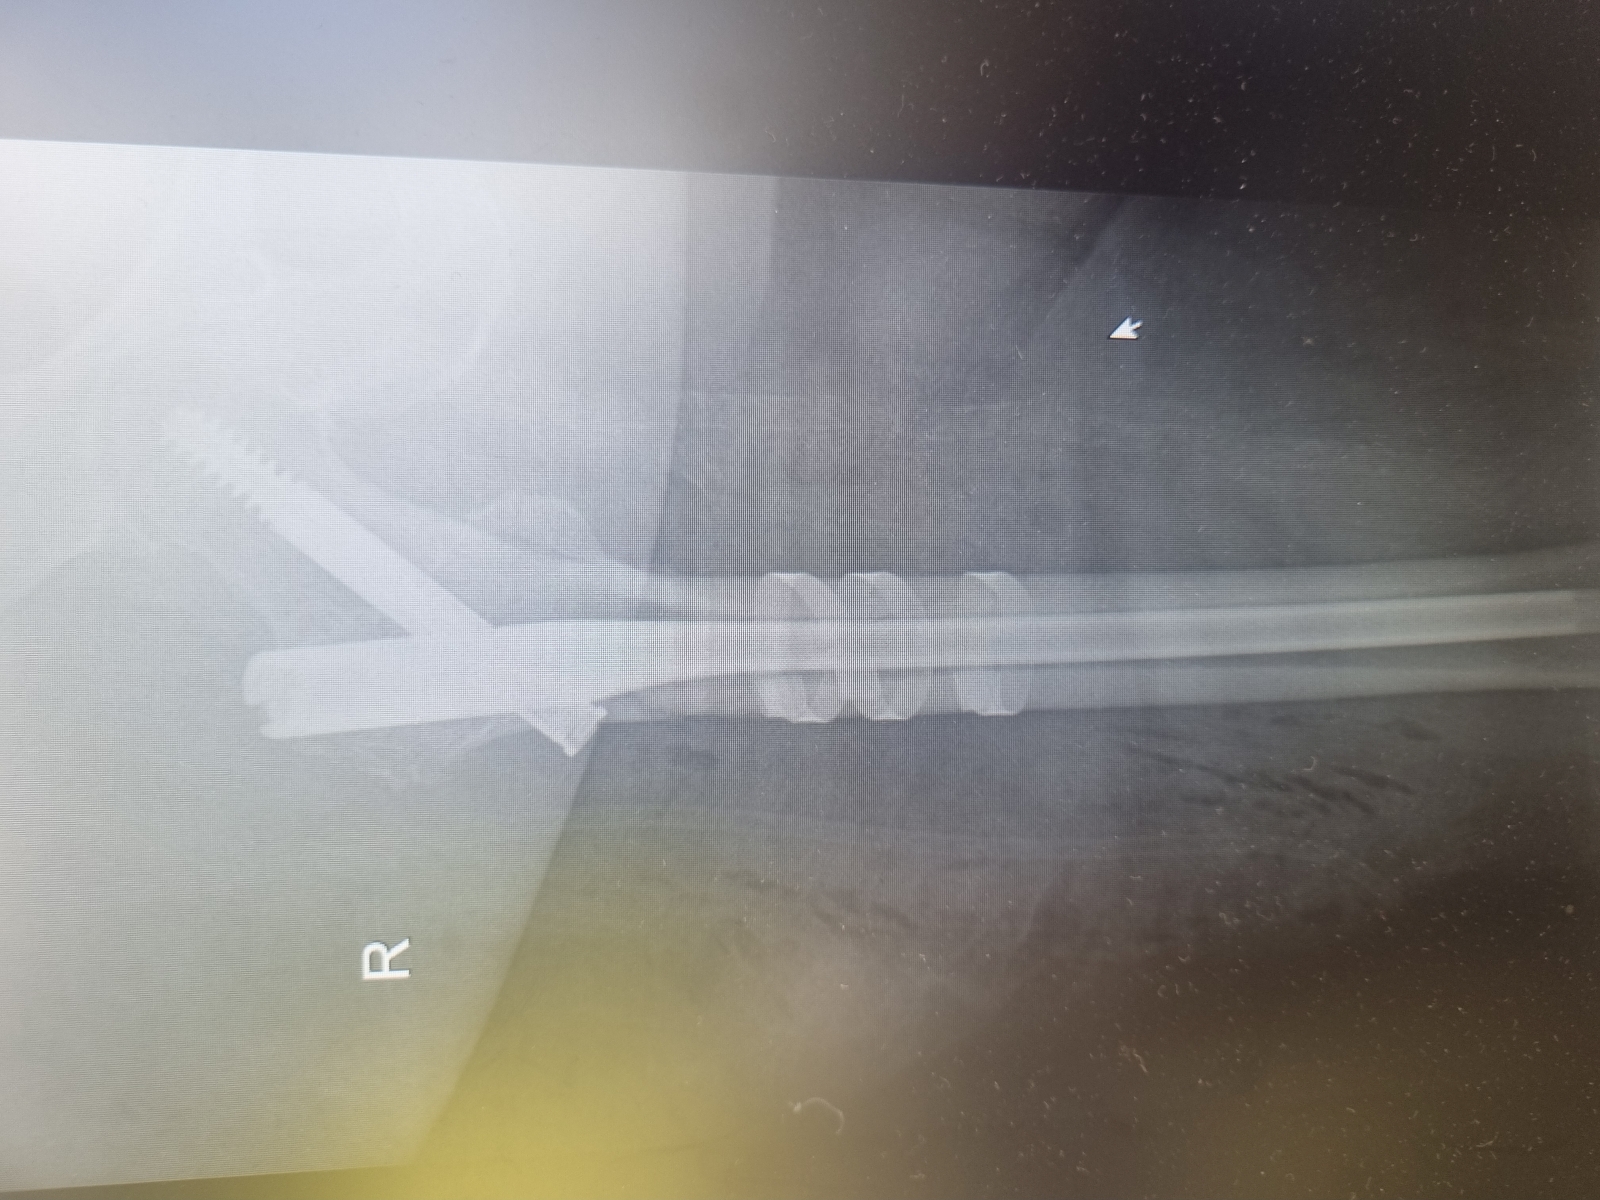

Zabiegi

Miednica i kończyna dolna